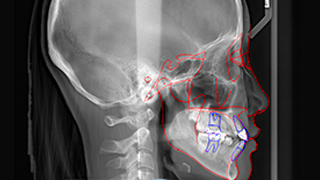

SMILE FACE DENTAL CLINIC’s 12-step orthodontic diagnostic system is an advanced process that systematically analyzes a patient’s teeth, jaw structure, facial balance, and bite, allowing us to establish the most optimal treatment plan.

01 Medical history review and personalized one-on-one consultation

02 Panoramic X-ray imaging

03 Cephalometric (lateral skull) X-ray imaging

04 Jaw Joint Examination

05 Frontal X-ray

06 Oral Examination

07 Impression Taking

08 Bite Registration

09 Intraoral Photography

10 Facial Photography

11 V-ceph

12 Analysis and Treatment Planning